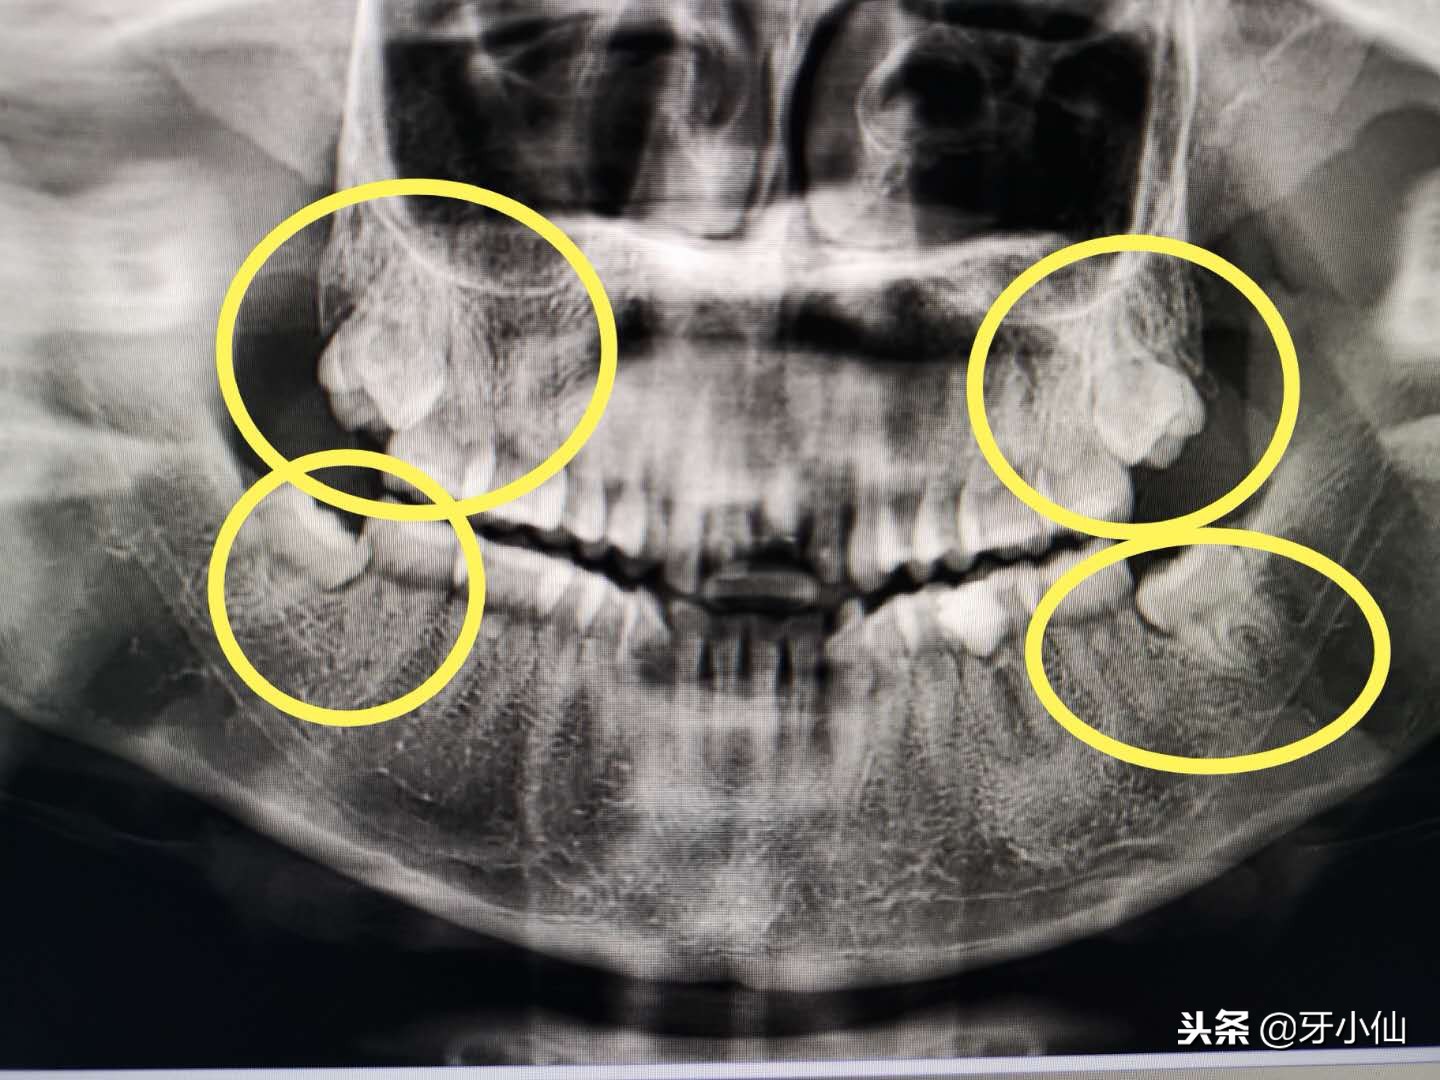

这四颗智齿都需要拔~